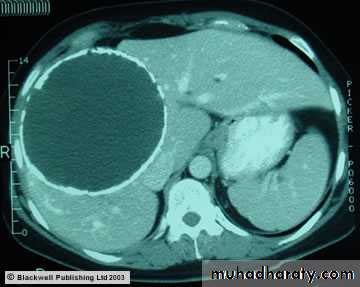

Abdominal CT Scan show. Large hepatic hydatid cyst